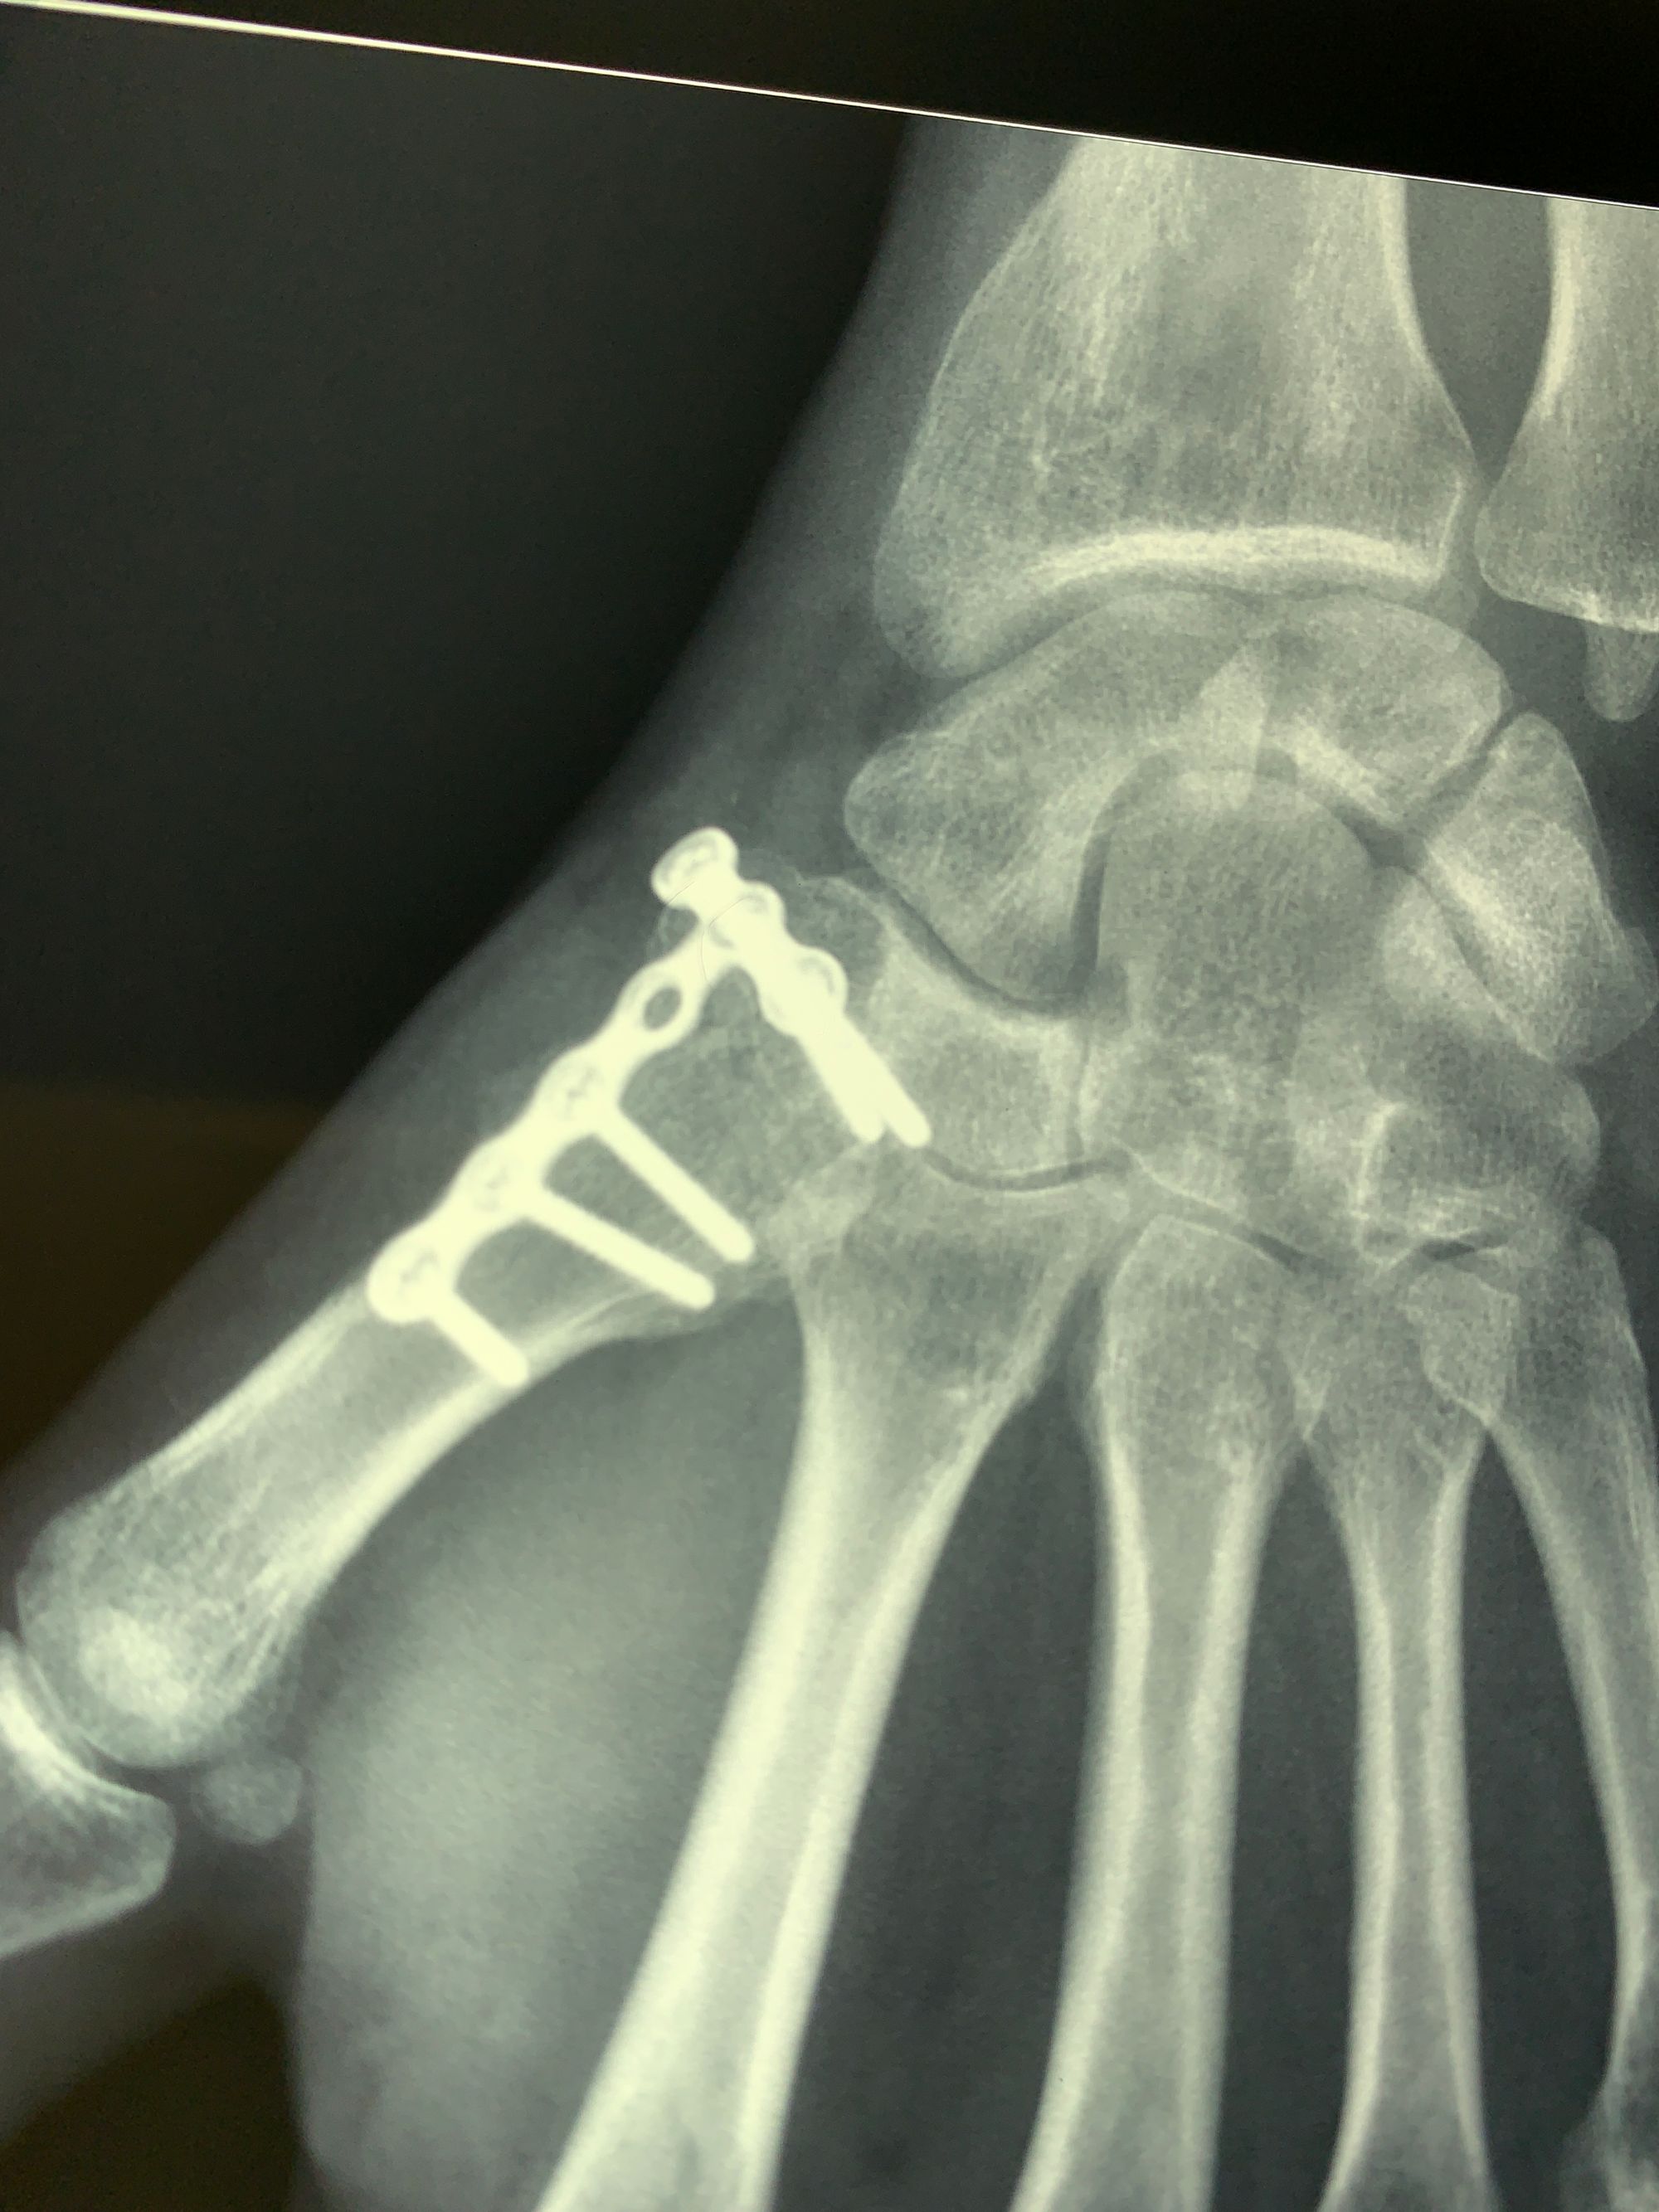

I have had good results with the PyroDisk™ implant (Integra) (Figure 14) which, thanks to a wide choice of sizes (diameter and thickness) is great at filling the gap left by the trapezium excision. Ligament reconstruction is used to stabilize the implant and metacarpal, which holds the thumb column in place and prevents any implant instability (series currently under review). Figure 15.